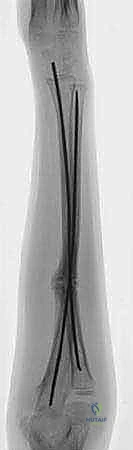

Nail Pattern and Placement

Multiple nail patterns have been described,6 but the standard is one medial and one lateral nail (

TECH FIG 4A,B

).

Alternately, if soft tissue compromise precludes the use of an entry site, the first nail is bent into a C shape, with the second bent into an S shape. The apex of the more distal curve in the nail should be at the fracture site.

The first nail is contoured into a C shape. It should be placed on the tibia and a fluoroscopic image obtained (

TECH FIG 4C,D

A gentle bend is placed in the nail, centered at the fracture.

The nail is placed up to the fracture site under fluoroscopic guidance. Initially, it is helpful to direct the bend posteriorly, as in the passage of a guidewire for a standard reamed nail, but it is important to rotate the bend into the proper plane to prevent a recurvatum deformity (

TECH FIG 4E,F

The second nail is placed in the same fashion.

1. The nails should be the same diameter to provide balanced fixation (FIG 4A).

2. Nails should be passed carefully to avoid the “creeping vine” effect.

3. If the nails spiral around each other, the elastic recoil, and thus the stability of the technique, will be lost (FIG 4B).

FIG 4 • Potential pitfalls in nail placement. A. The nails are of differing diameter, inducing a valgus moment that needs to be controlled in a cast. Note the incidental nonossifying fibroma. B. “Spiraling nails.” The elasticity afforded by three-point fixation is lost, making the construct less stable. POSTOPERATIVE CARE For patients treated with external fixation, a splint is used for 7 to 10 days to allow the tissues to recover.